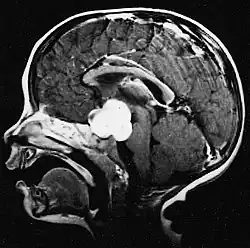

Usually – depending on the interview of the patient and after a clinical exam which includes a neurological exam and an ophthalmological exam – a CT scan and/or an MRI scan will be performed to confirm the presence of a tumor. They are usually easily distinguishable from normal brain structures using these imaging techniques. A special dye may be injected into a vein before these scans to provide contrast and make tumors easier to identify. Pilocytic astrocytomas are typically clearly visible on such scans, but it is often difficult to say based on imaging alone what type of tumor is present.

Pilocytic astrocytomas are often cystic tumors, and, if solid, tend to be well-circumscribed.